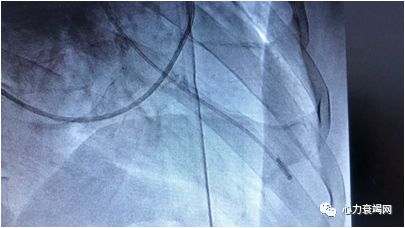

酒精消融术

室间隔中下部增厚20mm,切除心肌5.0g

室间隔至心尖有肌束连接

血流动力学检查对指导临床治疗非常重要